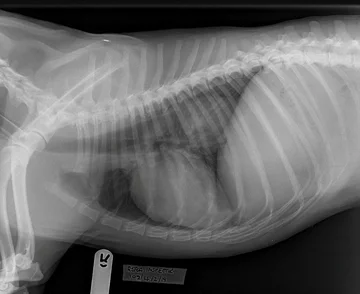

• Prześwietlenie pokazało, skąd dolegliwości psa

Prześwietlenie pokazało, skąd dolegliwości psa